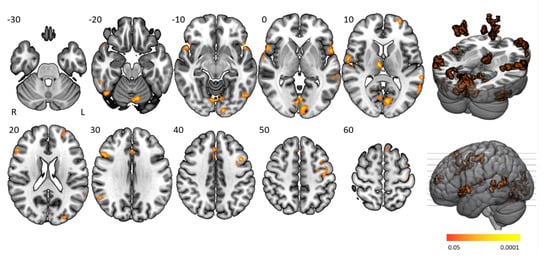

3.4. Time-On-Task Effects

Time-on-task analyses comparing BOLD signals in repetition 1 and 4 between participant groups yielded no significant activation differences. Time-on-task within blocks analyses demonstrated that people with narcolepsy type 1 had significantly less activation than controls in the “late half > early half” contrast combining the two difficulty levels. Post-hoc analyses showed that this effect was driven by the higher difficulty level, as shown in Figure 4 and Table 3. Significantly lower activation was found in people with narcolepsy type 1 in regions including the cingulo-opercular network (bilateral insula and operculum, left anterior cingulate cortex, right middle frontal gyrus, and thalamus), frontoparietal network (bilateral superior frontal gyrus, midcingulate cortex and right inferior frontal gyrus, and angular gyrus), (regulatory) motor areas, and visual regions. Other activated regions were the bilateral temporal lobe and inferior orbitofrontal gyrus and the right angular gyrus. The between-group differences were mainly driven by controls upregulating their neural efforts within higher difficulty blocks, whereas people with narcolepsy type 1 maintained stable activation over time. Decreased activation over time was only seen in those with narcolepsy type 1, in the visual cortex and cerebellum. No between-group time-on-task within blocks differences were seen in difficulty level 1.